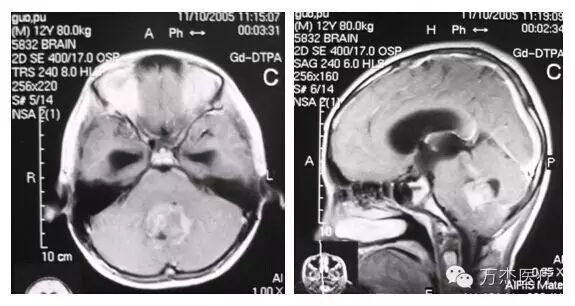

髓母细胞瘤是最常见的儿童肿瘤之一,在10岁以下的儿童中,发病率约占全部肿瘤的20%~30%,发病高峰年龄为5岁,男性略多于女性。该肿瘤位于后颈凹,在小脑蚓部和第四脑室中线附近,晚期肿瘤在脑脊液内播散。典型的临床表现主要与肿瘤占据后颅窝,堵塞第四脑室或中脑导水管引起的颅内压增高相关的症状:头疼,恶心,呕吐,视物模糊,以及肿瘤压迫小脑所致的平衡功能障碍,如走路